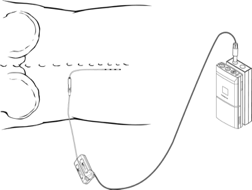

Εικόνα 16.3. Σχεδιάγραμμα που βοηθά στην κατανόηση της διαδικασίας της δοκιμαστικής ηλεκτρικής διέγερσης, και δείχνει το λεπτό κυλινδρικό ηλεκτρόδιο, το οποίο εισάγεται με ελάχιστα επεμβατική τεχνική, διαδερμικά (όπως μία σύριγγα ενέσεως) υπό τοπική αναισθησία, και την σύνδεση του ηλεκτροδίου με την εξωτερική συσκευή διέγερσης. Αυτή η τεχνική εφαρμόζεται προσωρινά για να διαπιστωθεί εάν η ηλεκτρική διέγερση (επισκληρίδιος νωτιαίου μυελού ή περιφερικού νευρικού πεδίου) μπορεί να σταματά τον πόνο.